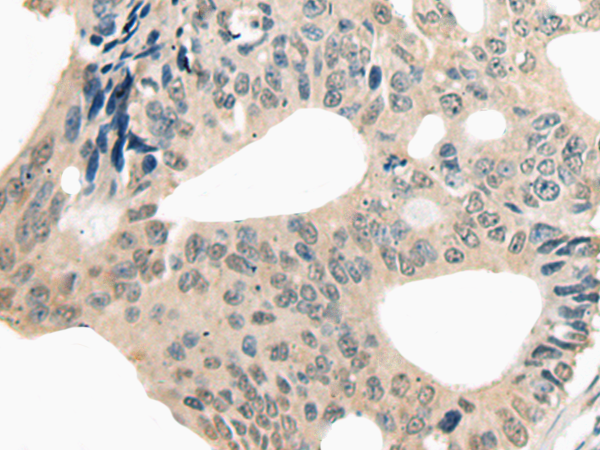

IHC positive control: |

Human colorectal cancer |

IHC Recommend dilution: |

20-100 |